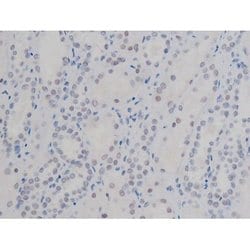

Invitrogen™ Phospho-NPM1 (Thr199) Polyclonal Antibody

Antibody detects endogenous levels of Nucleophosmin only when phosphorylated at Threonine 199.

| Applications | Immunohistochemistry (Paraffin), Western Blot, Immunocytochemistry |